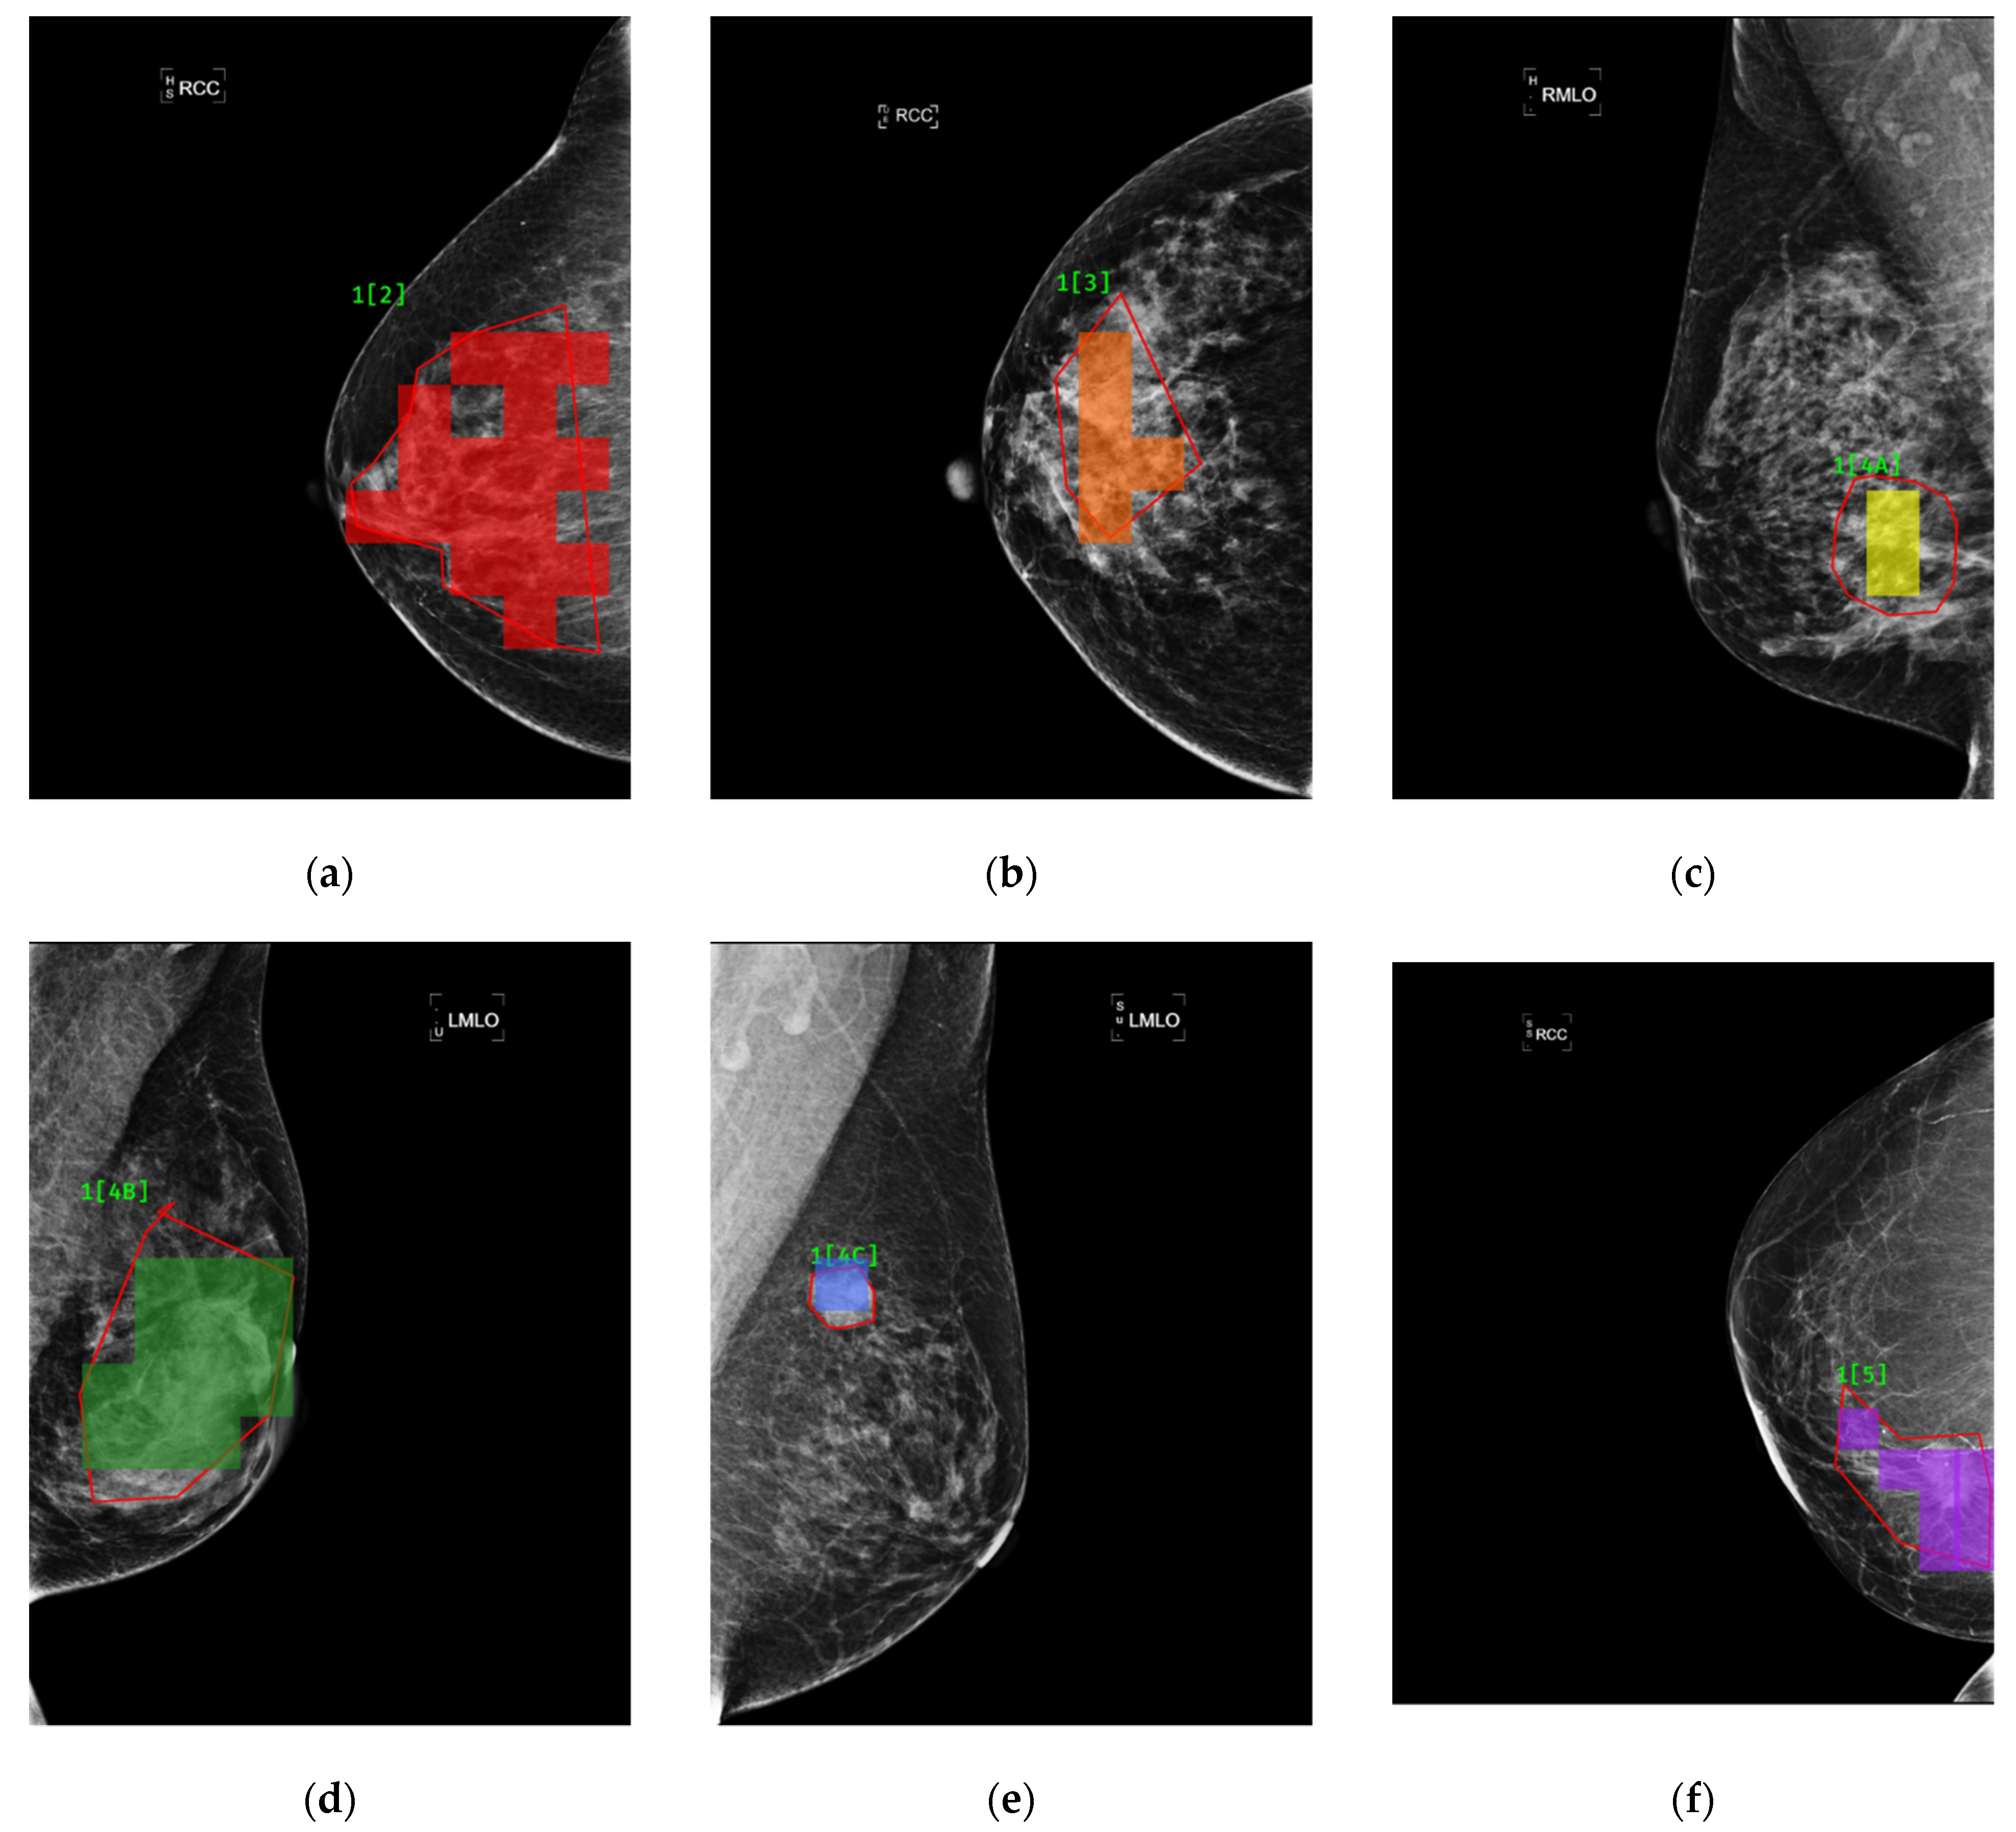

The outperformance of this model was indicated by an overall accuracy of 94.22%, an average sensitivity of 95.31% and an average specificity of 99.15%. As can be found in Figure 11, there is a good agreement between the red framed ground truth and the blocks, highlighted in color, in each of the mammograms in Figure 11a–f, where findings were classified as BI-RADS categories 2–5, respectively.

Figure 11. Comparisons between findings labeled by radiologists (framed in red) and highlighted in color in the cases of BI-RADS category 2, 3, 4A, 4B, 4C and 5 lesions in (af), respectively.